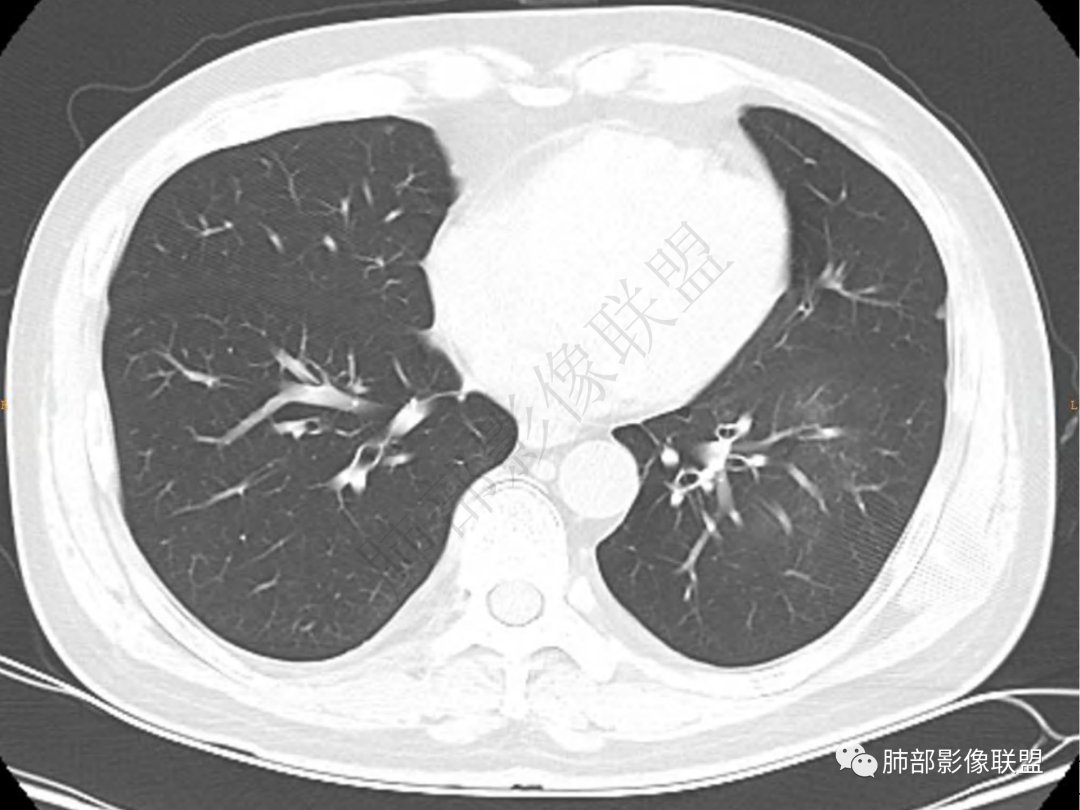

2.左肺下叶团片影,跨背段及内前基底段,实性部分类椭圆形,密度不甚均匀,可见毛刺及棘状突起,未见典型分叶及胸膜凹陷。病灶上下缘可见相应肺段支气管旁进侧出,管壁轻度增厚,未见狭窄阻塞。

3.周边较大范围磨玻璃影,边界相当模糊,小叶增厚明显。注意叶裂另一侧、左肺舌段亦可见磨玻璃影及增厚的小叶间隔。未见明确卫星病灶。

1.病灶不够密实,没有典型分叶,收缩乏力等,支气管未见截断等,缺乏一般肿瘤性肿块特征。

2.周围磨玻璃影边界不清缺乏限制,甚至“激惹”到相邻肺叶,也许提示较明显的炎性水肿。

正如多数老师分析到的,本例病灶炎性特点比较明显。